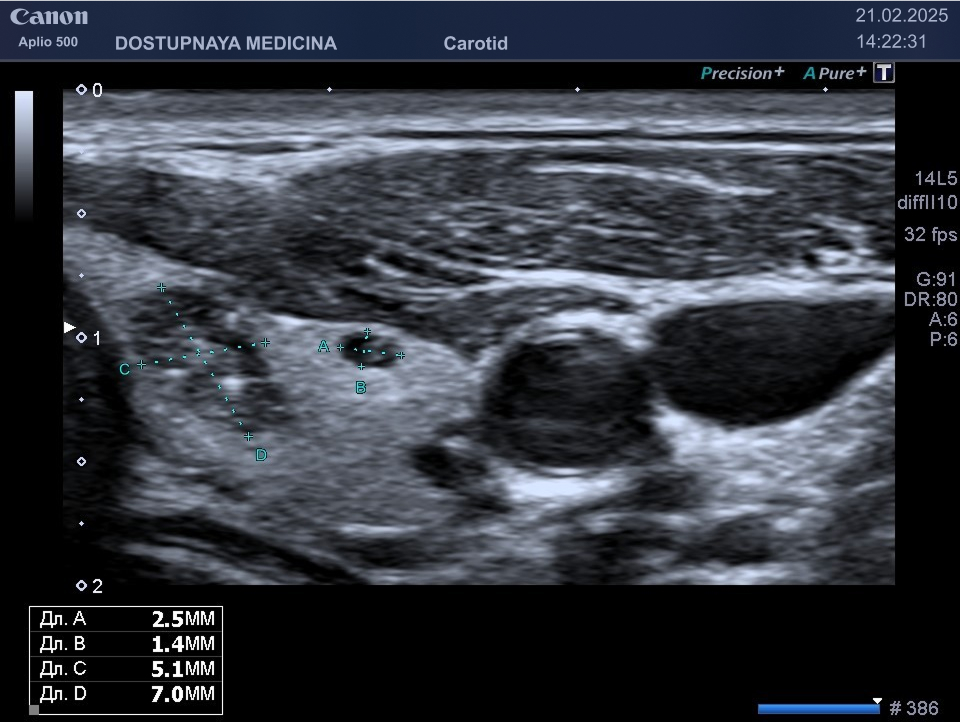

Узловые образования в щитовидной железе достаточно часто выявляются при ультразвуковом исследовании. Неоднократно я обнаруживал довольно большие объёмные образования в щитовидной железе у пациентов, которые приходили к нам в клинику по совершенно другому поводу, например, для ультразвукового исследования сосудов шеи. Многие из них утверждали, что их ничего не беспокоило и что гормоны щитовидной железы у них в анализах были в норме. Но дело в том, что узловые образования в щитовидной железе в большинстве случаев никак не влияют на уровень ТТГ, тироксина и трийодтиронина в крови. Тем не менее узловые образования в щитовидной желез почти всегда вызывают онконастороженность у врача. Примерно 1/3 людей планеты Земля имеются узловые образования в щитовидной железе. Понятно, что не у всех этих людей образования в щитовидной железе носят злокачественный характер. Но следует учитывать, что рак щитовидной железы довольно часто встречается у людей, в том числе и в молодом возрасте. Тем не менее ультразвуковому исследованию щитовидной железы большинство пациентов уделяют не столько много внимания, как к исследованию, например, органов брюшной полости или молочных желез.

В ультразвуковой диагностике существует классификация образований щитовидной желзы по TIRADS, которая по различным критериям определяет степень онкоопастности того или ионого узла. При оценке учитывается эхоструткура образования ( кистозная, губчатая, солидная или солидно-кистозная), эхогенность ( анэхогенное, гиперэхогенное, гипоэхогенное), пространственная ориентация горизонтальная, вертикальная, неопределённая), контуры образования (ровные, дольчатые, зазубренные с острыми углами), наличие эхогенных включений( макрокальцинаты, микрокальцинаты, периферическая кольцевидная кальцификация). В зависимости от этих критериев выделяют различные категориии объёмных образований в щитовидной железе:

Большинство узловых образований в щитовидной железе не нуждаются в лечении и требуют лишь наблюдения путём повторного ультразвуковых исследований.

При подозрении на озлокачествление и увеличении узла в размерах требуется тонкоигольная пункционная биопсия с полседующим цитологическим исследованием, полученного материала.